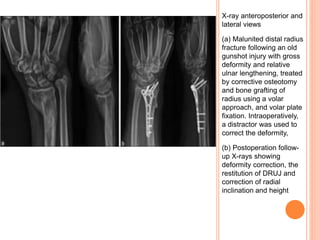

X-ray anteroposterior and

lateral views

(a) Malunited distal radius

fracture following an old

gunshot injury with gross

deformity and relative

ulnar lengthening, treated

by corrective osteotomy

and bone grafting of

radius using a volar

approach, and volar plate

fixation. Intraoperatively,

a distractor was used to

correct the deformity,

(b) Postoperation follow-

up X-rays showing

deformity correction, the

restitution of DRUJ and

correction of radial

inclination and height